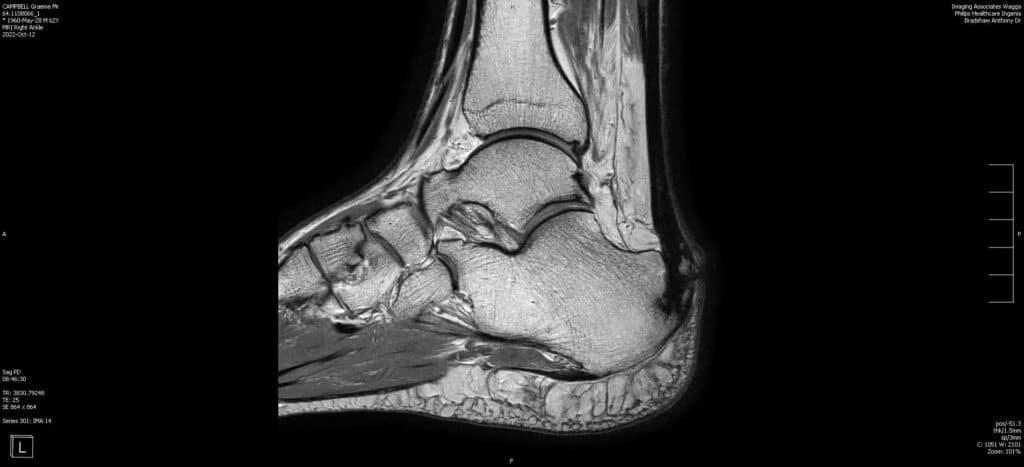

Inflammation of the Achilles’ tendon where it inserts into the calcaneus (heel bone) is known as insertional tendonitis. It is often associated with an abnormal bony prominence just deep to the tendon known as Haglund’s deformity or pump bump. This may play a role in rubbing on the deep aspect of the tendon to cause pain and inflammation in the tendon and surrounding soft tissues. If large enough, it can also rub on footwear or even prevent the wearing of certain shoes.

The form of operative management is dependent on the degree of involvement of the Achilles’ tendon. When the tendon is not significantly involved, this condition can be managed arthroscopically. This involves 2 keyhole incisions next to the tendon through which a small camera and instrumentation can be inserted. The bursa (fluid containing sack deep to the tendon that will also be inflamed) is firstly excised, followed by the Haglund’s deformity, and finally the deep surface of the tendon is inspected. The advantage of this technique over an open (large incision) procedure is that the rehabilitation period can be accelerated.

If the Achilles’ tendon demonstrates extensive involvement on pre-operative scans or unexpectedly on arthroscopy, or if the Haglund’s deformity is too large to be safely removed by arthroscopic means, an open procedure is required. This allows removal of diseased tissue from within the Achilles’ tendon, safe excision of a large deformity, and repair of the tendon to the calcaneal bone.